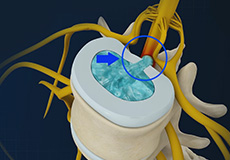

Disc Herniation

Disc herniation is a condition where the central nucleus pushes through the outer edge of the disc, causing a bulge that compresses the spinal nerves.

Lumbar Herniated Disc

A herniated disc is a condition in which the outer fibers (annulus) of the intervertebral disc are damaged, causing the soft inner material of the nucleus pulposus to rupture out of its space. It is the most common cause of lower back pain and pain that radiates down the leg (radiculopathy).

Herniated Disc (Lumbar)

Herniated disc is a condition in which the outer fibers (annulus) of the intervertebral disc are damaged causing the soft inner material of the nucleus pulposus to rupture out of its space. A herniated disc, common in the lower back (lumbar spine) occurs when there is a tear in the outer lining of the disc (annulus fibrosus). This causes the inner jelly-like material (nucleus pulposus) to leak out and place pressure on the adjacent spinal nerve root. It is the most common cause of lower back pain and pain that radiates down the leg (radiculopathy).